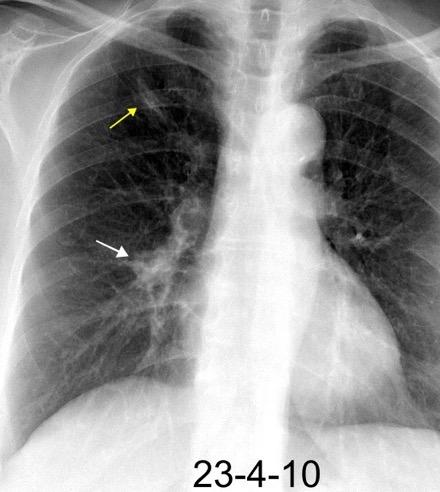

WINDEMERE” . SÍNDROME DE LADY

Forma indolente. Supresión de la tos. Língula y LM los más frecuentemente afectados. Bronquiectasias.

Coexistencia con nódulos centrilobulillares y patrón en mosaico muy sugerente.

Micobacteria atípica

Frecuencia en “clusters” familiares. Factores genéticos de sensibilidad del huésped a la infección pulmonar.

Colombo RE et al. Familial Clustering of Pulmonary Nontuberculous Mycobacterial Disease. Chest 2010./ Olivier KN. Lady Windermere Dissected: More Form Than Fastidious. Ann Am Thorac Soc. 2016/Martínez S et al. The many faces of pulmonary Nontuberculous Mycobacterial infection. AJR. 2007